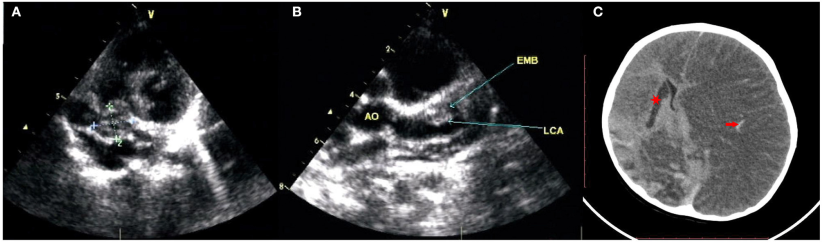

由于CAT的存在和CAL的快速进展,建议使用抗凝剂(华法林)和溶栓剂(低分子肝素(LMWH)或组织型纤溶酶原激活剂),但孩子的父母因不便而拒绝监测国际标准化比率(INR)和潜在的出血并发症,尽管反复向他们解释溶栓治疗的必要性。在后续的随访中,患儿父母仅同意氯吡格雷(1 mg/kg/天)和阿司匹林(5 mg/kg/天)维持治疗,CAT和CAA保持不变,没有进展或消退(图1A,B)。

图1. 超声心动图显示广泛的CAA和CAT

不幸的是,出院5天后,患儿的临床状况突然恶化,出现抽搐、意识不清、心律不齐。复查头颅CT显示除既往右侧基底节脑梗死外,出现累及整个左侧大脑区域的出血性卒中,并伴有明显的继发性脑肿胀和水肿(图1C)。这可能是由先前溶栓治疗的出血并发症引起的。严重的脑疝发展迅速。遗憾的是,患儿父母因经济因素和预后不佳而退出治疗,患儿很快死亡。